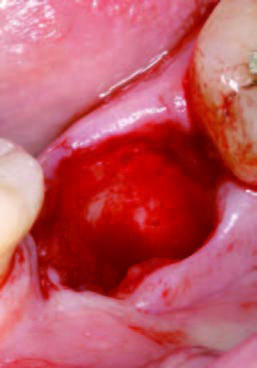

PRGFなし

抜歯直後

抜歯後にできた穴にPRGFを注入すると、上皮や骨の再生が促進され、短期間で穴が塞がります。また、抜歯後の痛みや腫れも軽減されるため、回復がスムーズに進みます。

一方、自然治癒の場合、穴が完全に塞がるまでに数ヶ月かかることがあります。その間に、ドライソケット(抜歯窩治癒不全)を引き起こしたり、食べ物が詰まることで痛みや悪臭が発生することもあります。